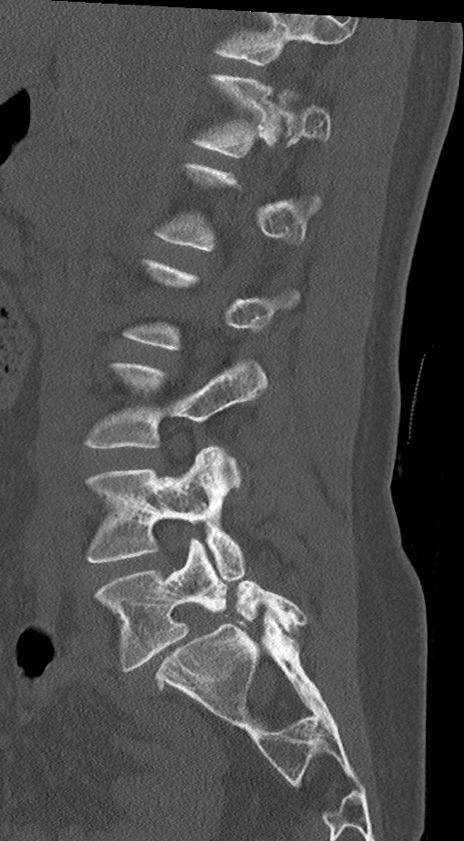

【整形】TIPS症例4 腰椎CT(矢状断像)

腰椎CT

冠状断像